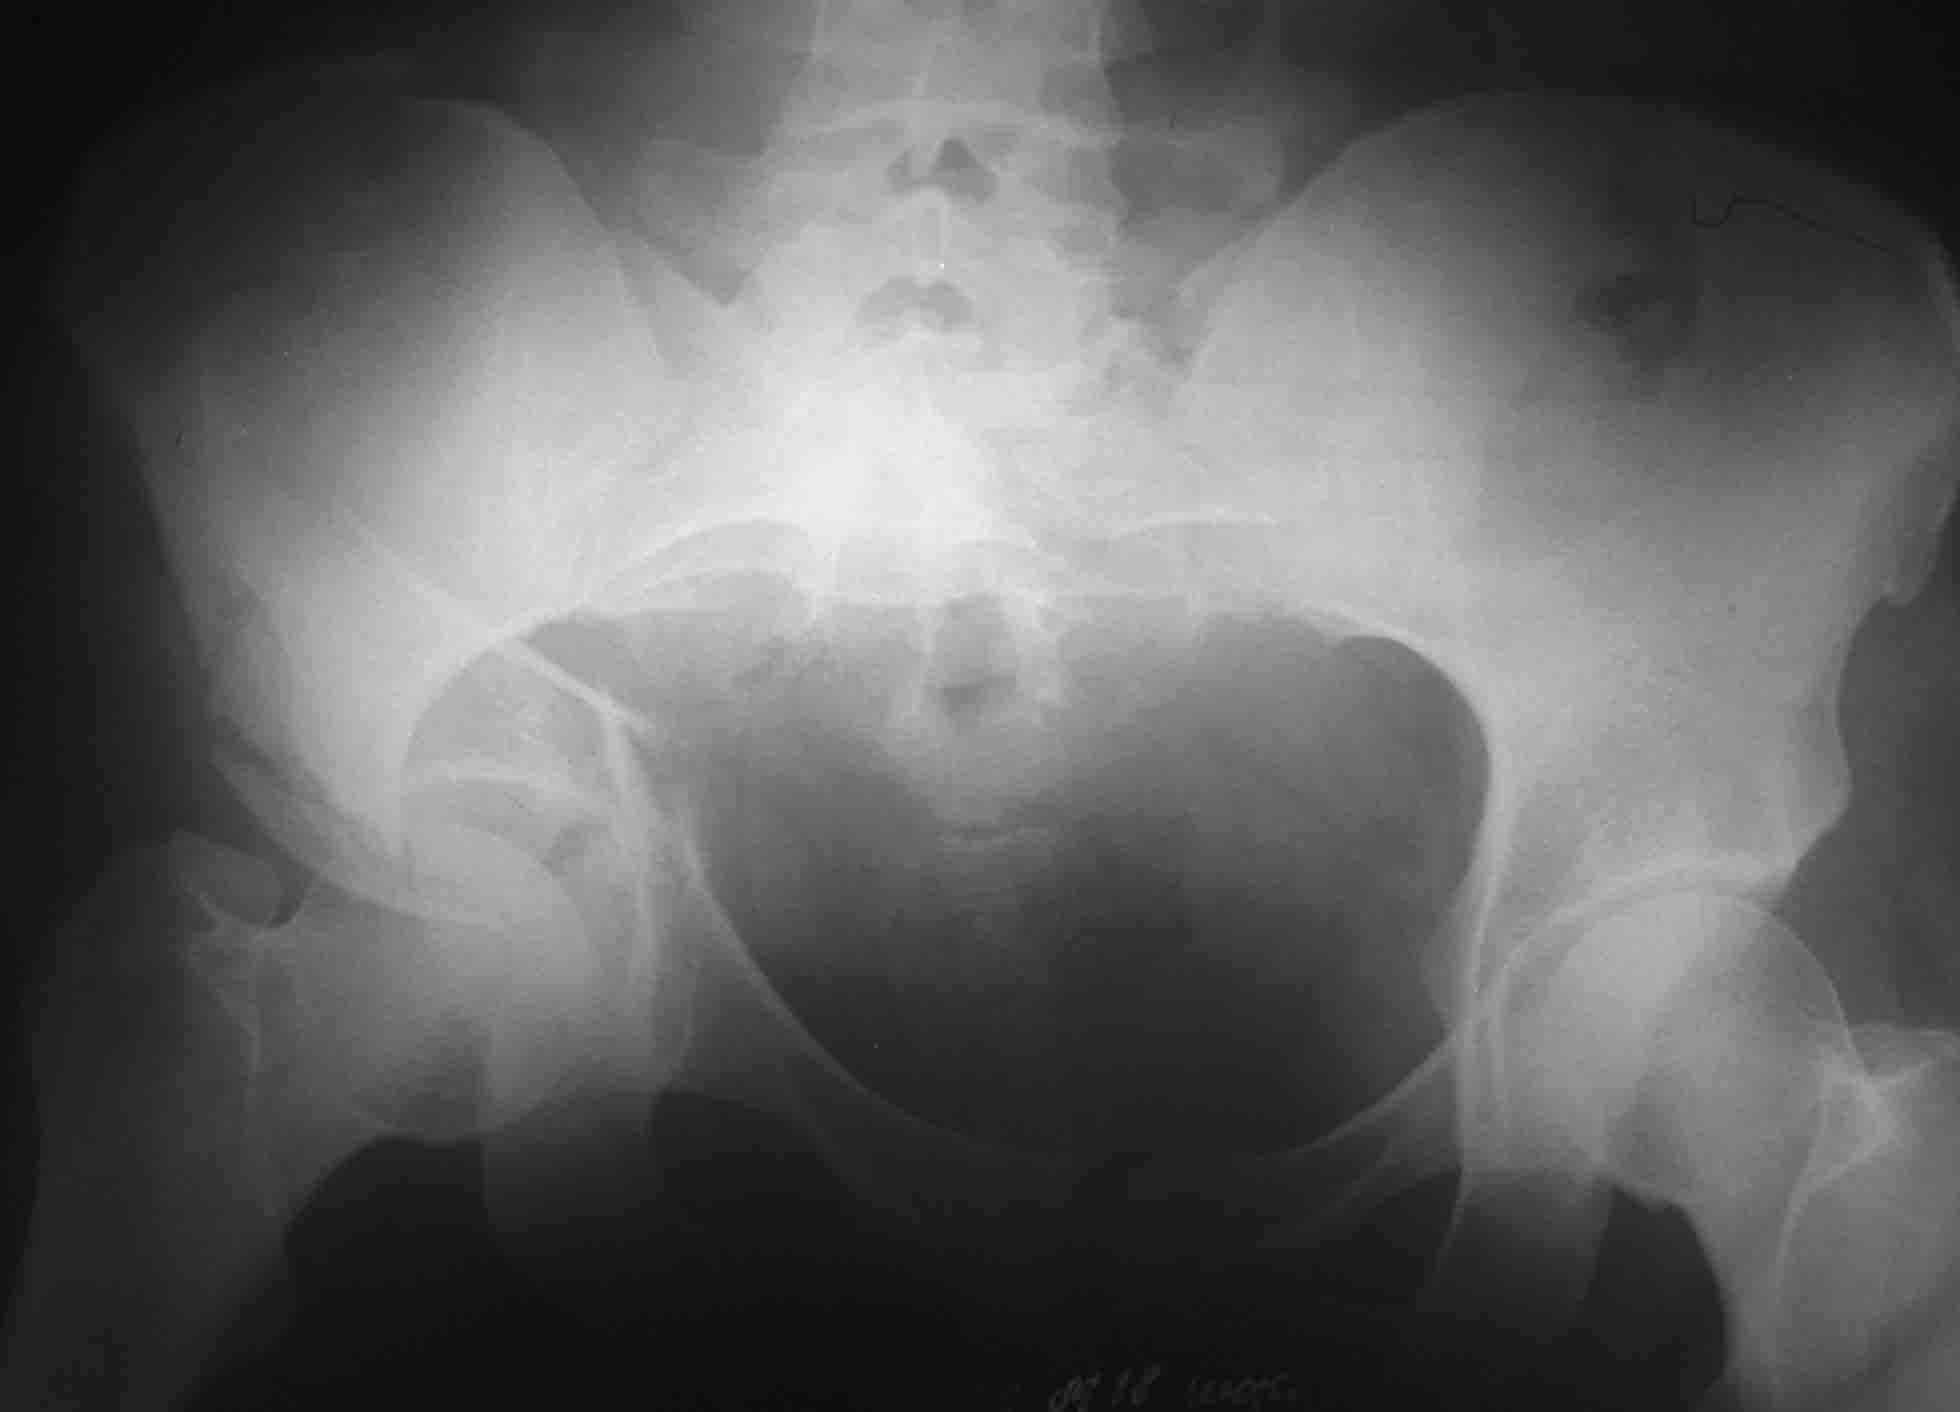

Пациентка 26 лет поступила в больницу 9 дней назад после кататравмы (падение с 4-го этажа) Тяжелая сочетанная травма: Ушиб головного мозга средней тяжести.З/полифокальный перелом таза (оскольчатый чрезвертлужный справа, латеральной массы крестца слева со смещением отломков. З/оскольчатый перелом н/3 правого бедра. З/оскольчатый перелом правой пяточной кости. Тупая травма живота - разрыв слизистой толст кишечника, кисты яичника.

При поступлении - лапаротомия, ушивание ран кишечника, резекция кисты; скелетное вытяжение за правую н/конечность (бугрист б/б кости) На 2-й день на таз наложен стержневой аппарат из "того что было" (по паре стержней в подвздош кости) - естественно, при таком переломе фиксации таким аппартом практически никакой. Пациентка 2 дня назад переведена из реанимации в травм отделение, состояние средней тяжести, показатели красной крови - эритр 2,7; Гб - 75 г/л; Спицевое вытяжение за б/вертел не накладывали из-за возможности инфицирования бедра (пациенка по комплекции довольно упитанная) Встает вопрос - что и в какой последовательности делать с поврежденными сегментами скелета? Думали о варианте: Первым этапом - погружной остеосинтез бедра (DCS? интерлокинг?)и ,возможно, пяточной кости.Вторым этапом - стержневой остеосинтез таза с бедренным модулем (внутренний остеосинтез таза, думаю, по соматике пациентки будет возможен не скоро)